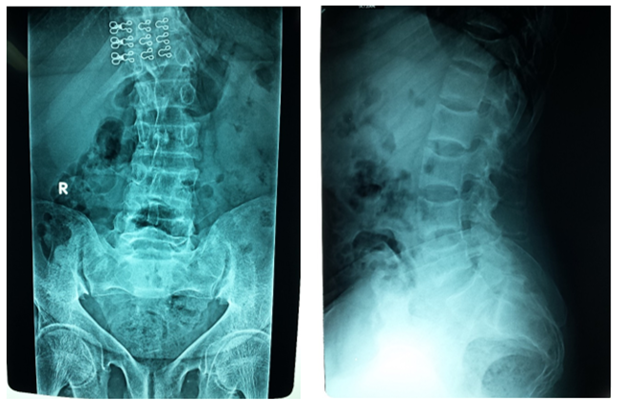

The Pelvis is markedly triradiate, with coarsening of the trabeculation of the femoral head and neck. The femoral heads have lost their normal smooth rounded outline, and are now showing relative flattening, there is a linear translucency in the sub-trochanteric region of the left femur and right inferior pubic ramus suggesting Looser’s zones Figure 4–7. The most impressive features of osteomalacia are the x-ray findings of what is considered to be diagnostic in osteomalacia. Pathologically, they are pseudo fractures except might rarely be present in Paget's disease. It appears as a thin, translucent band. Looser's zones are incomplete stress fractures that heal with callus which is poorly mineralized by calcium. They are frequently seen in the pubic bone, the necks of the femurs, and less frequently humerus and at the edge of the scapulae Figure 8.

Figure 5 Right) Frontal X-ray of LSS shows marked scoliosis and there is subchondral resorption of the right sacro-iliac joint. (Left) Lateral X-ray of LSS shows biconcave appearance of the vertebral endplates (codfish vertebrae) with marked osteopenia. There is spondylolysis of L5 on S1 and there is pathological pedicles fractures of L5. There is overall noticeable diffused osteopenia.